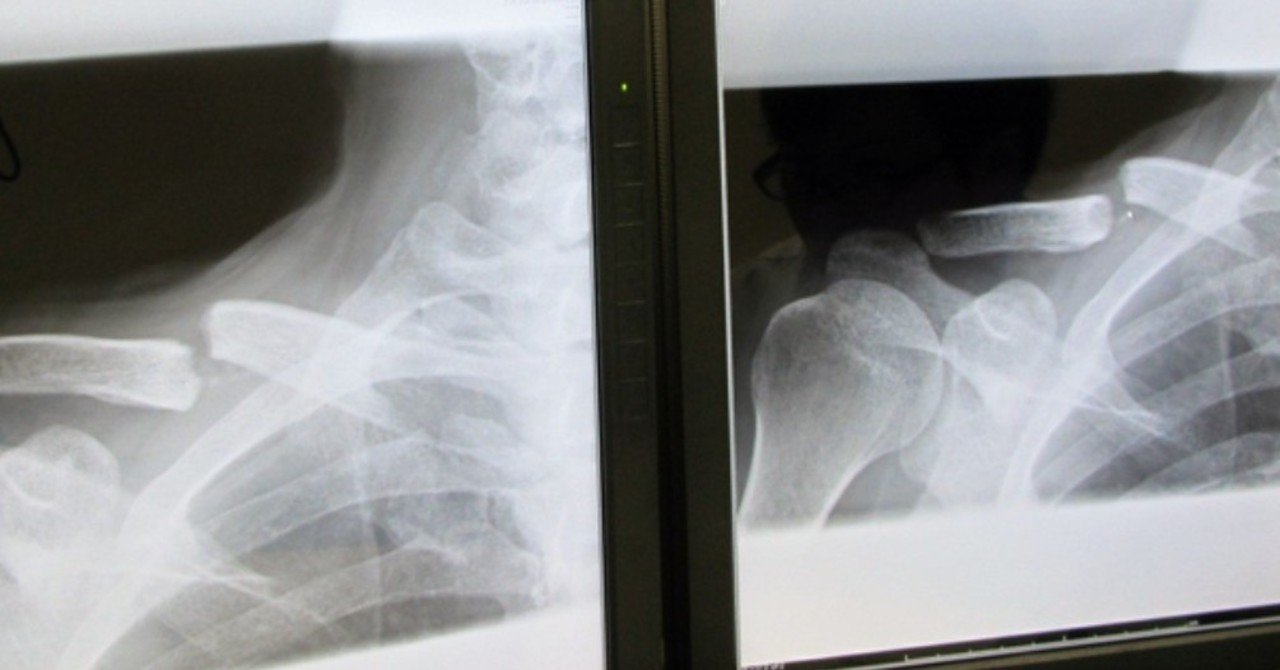

鎖骨骨折 鎖骨骨折はスポーツ外傷では頻度が高く、受傷原因は肩鎖関節脱臼とほぼ同様です。 肩前面の鎖骨中央部の圧痛、腫張、変形(写真3)を呈し、肩の挙上に際しては激痛が生じます。 治療は8字帯(約6~8週間)を用いた保存療法が原則ですが骨折部の ズレが大きかったり 、 骨が外に飛び出す ような 開放骨折 や鎖骨の下にある 神経や血管 が傷ついているような場合は 手術 が行われます。 手術には、 鎖骨の中に鋼線を入れて固定 する方法( 髄内釘固定 )や金属の板を鎖骨にあてて 螺子で固定 する方法( プレート固定 )などが 鎖骨骨折ほど痛みはありませんが、肩鎖関節部分に圧痛があります。鎖骨遠位端の突出と変形が見られます。 肩鎖関節脱臼の処置は、 90 °に曲げた肘を上に押し上げ、鎖骨の端を上方から圧迫しテーピングをして、三角巾で固定します。